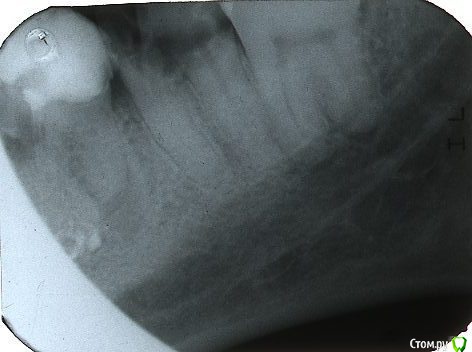

stomt Опубликовано 14 июня, 2017 Автор Поделиться Опубликовано 14 июня, 2017 (изменено) Вот запоздалый снимок ибо когда я его сделал -- то вечером (скоро неделя будет) эта стенка хруснула, со стороны надлома очевидно, то есть соседнего более переднего зуба который зацементированый пломбой. Это сталось потому что боль уже ушла и помалу пытался есть этим осколком зуба. Не знаю на чем теперь стенка держится, но движется очень вольготно -- надо очевидно новый снимок делать.Но вы хоть подскажите -- возможно ли было спилять стенку перед этим до основание, и возможно ли это сделать теперь, ибо я не знаю за что она там держится -- за 10-20% линии соприкосновение, или за десну?Во внешнюю сторону стенка так на 20-30 градусов легко отклоняется -- во внутреннюю сторону -- НЕТ -- упирается. И держится со стороны разве зуба р мудрости который хорошо виден на снимке -- но на поверхности только один внешний зубец имеет выход.Очевидно что прежде вариант хирурга был проще -- надо и теперь стенку хирургически удалять -- или можно как-то вручную? Изменено 14 июня, 2017 пользователем stomt Ссылка на комментарий

DmitrySH Опубликовано 14 июня, 2017 Поделиться Опубликовано 14 июня, 2017 (изменено) Удаляйте + шестой тоже кандидат на удаление Изменено 14 июня, 2017 пользователем DmitrySH 1 Ссылка на комментарий

red_butler Опубликовано 15 июня, 2017 Поделиться Опубликовано 15 июня, 2017 Шестой и седьмой зубы нужно удалять, причина степень их разрушения. Ссылка на комментарий

stomt Опубликовано 17 июня, 2017 Автор Поделиться Опубликовано 17 июня, 2017 (изменено) Я эти все вопросы задаю касательно вопроса пломбирования. Если делать панораму -- так уже к другому доктору надо обращатся, и там уже уж точно просто не обойдется. Здесь врач по максимуму пытается беречь зубы -- врач все таки не последний, хотя возрастной профильный контингент у нее другой.В этом случае -- врач просто одним движением руки сломал эту колебающуюся стенку -- и не надо было к хирургу обращатся. Сперва было чуство что со стенкой выдернула и половину корня -- но нет -- ровно по уровню уже достаточно испиляного пару лет назад корня (так на 2-3 мм. ниже уровня десны). Говорит что корни целые -- потому надо сперва их лечит. Судя по фото пленки зуба -- что можно сделать, если учесть что есть соседней зуб мудрости -- или его в принципе не используют? (и на верх вылезла лиш его первая половина).Хотя не понимаю как могут быть проблемы с какими то установками (не р-н поликлиника же), чтобы ничего не делать. Изменено 17 июня, 2017 пользователем stomt Ссылка на комментарий

stomt Опубликовано 17 июня, 2017 Автор Поделиться Опубликовано 17 июня, 2017 На фотке три (с зубом мудрости) крайних левых нижних зуба. Ну поставит пломбу может временную на этот зуб врач -- хотя есть сомнение что она будет держатся, ибо предыдущая "отклеилась" очень быстро как "карамель" (то есть никак ни держалась) и осталась "стенка".А вопрос к форуму -- какую конструкцию здесь можно применить на эти два разрушеных зуба -- штыри? Можно ли использовать зуб мудрости? Ссылка на комментарий